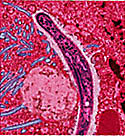

Малярия - это потенциально смертельное заболевания, которое вызывают паразиты, переносимые комарами. Для людей опасны несколько видов таких паразитов: Plasmodium falciparum, Plasmodium vivax, Plasmodium malaria и Plasmodium ovale. Каждый вид вызывает болезнь с немного разными симптомами. Как только такой паразит добирается по кровотоку к печени человека, развивается малярия.

• Инфицированного кусает не заражённый комар. В момент, когда комар пьёт кровь, в его организм попадают гаметоциты (можно сказать, половые клетки) паразита.

• Теперь инфицированный комар кусает кого-то ещё и передаёт паразитов здоровому человеку.

• В организме своего нового носителя, паразиты направляются к печени. Там они могут находиться несколько месяцев или даже год в спящем состоянии. В это время у заражённого может и вовсе не быть симптомов.

• Паразиты растут и развиваются. Как только они достигают зрелости, они выходят из печени в кровоток. Именно в этот момент проявляются первые симптомы малярии.

• Такого человека с малярией может снова укусить здоровый комар. Этот комар снова может передать малярию здоровому человеку, если укусит кого-то ещё. И цикл начинается снова.